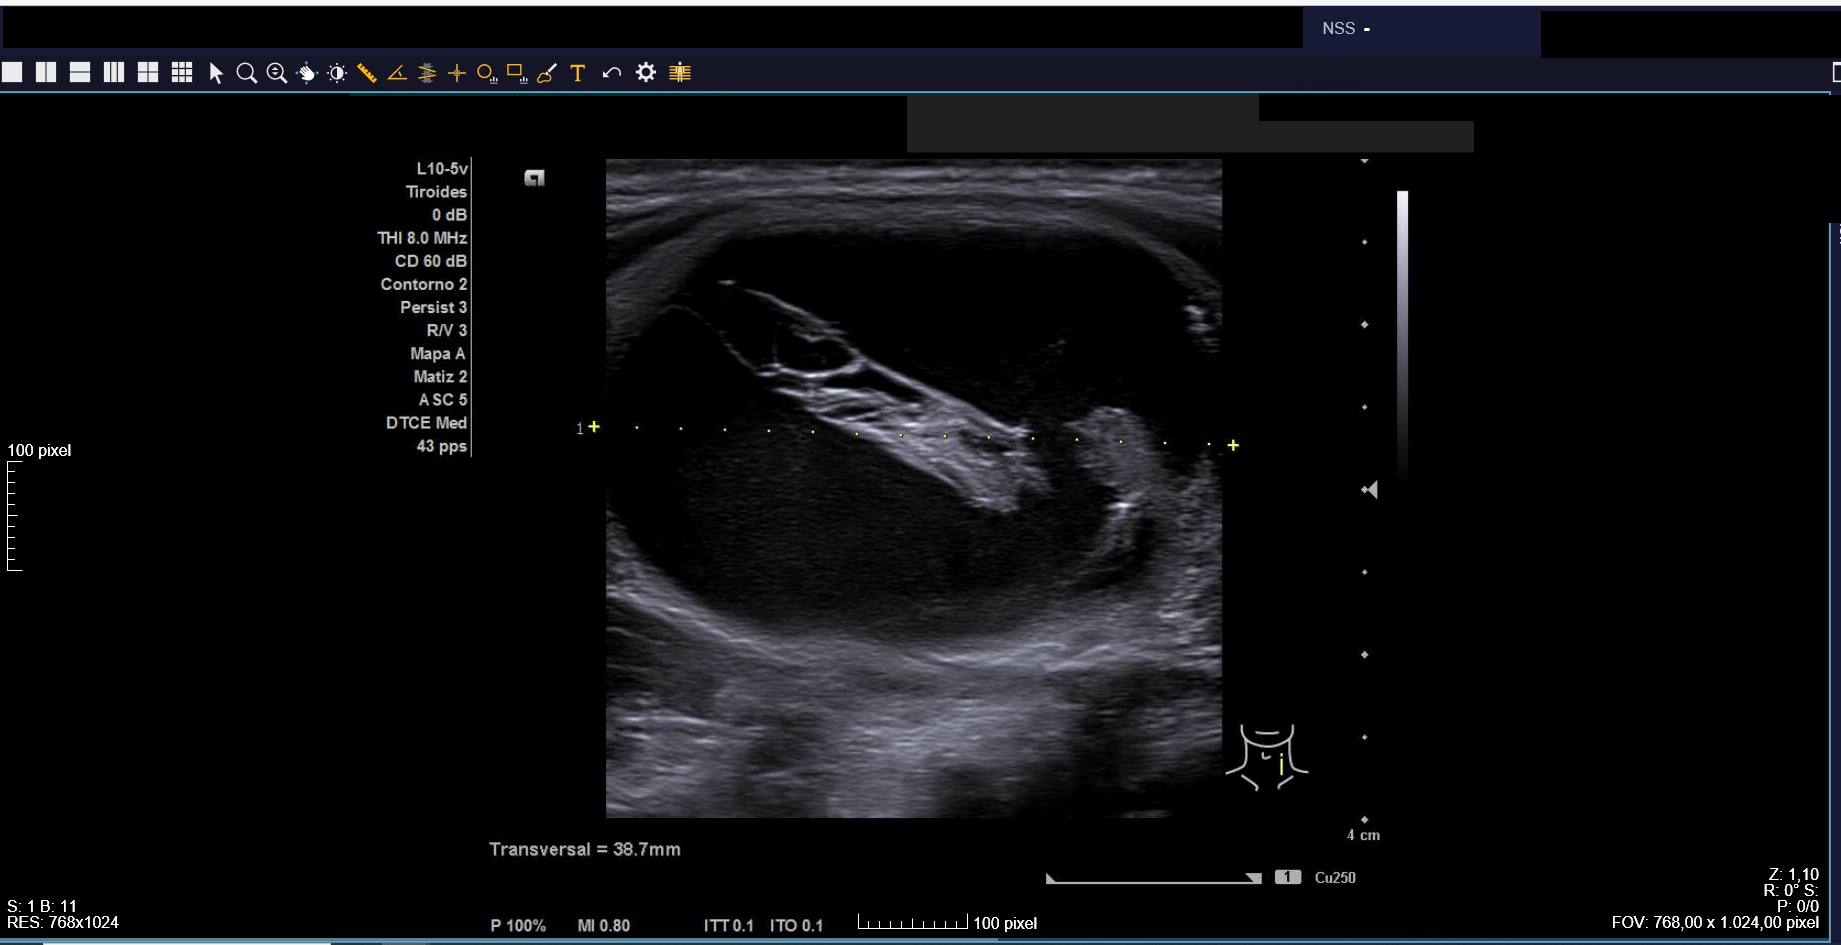

Ecografía clínica: tiroides de tamaño normal con ecoestructura homogénea. En lóbulo tiroideo izquierdo nódulo de 3 cm, anecoico, márgenes bien definidos con imagen hiperecoica en su interior (Imágenes 1, 2 y 3).